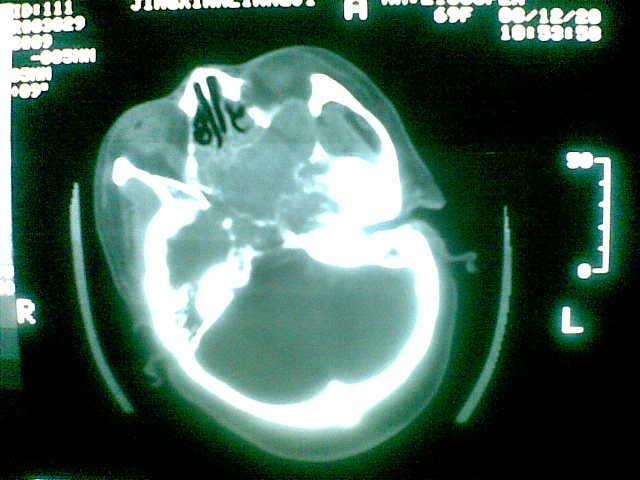

69岁 女 主因头痛就诊。大家看看起源于哪里啊

起源于斜坡,考虑脊索瘤.

考虑脊索瘤(起源于蝶枕联合部)。

颅底骨质破坏伴软组织密度影、斑片状高密度(死骨影)。

考虑:脊索瘤。

多为脊索瘤。起源于斜坡!

支持;脊索瘤诊断。图片质量太差了。

考虑起源于斜坡的脊索瘤。血管瘤待排。